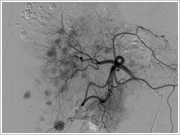

2. 血管造影検査

血管造影検査室では、主に心臓以外の血管をカテーテルで造影して診断、治療を行っていきます。

こちらの検査室では、立体的な血管像やCTのような画像を作成することができ、診断や治療の確認に利用していきます。

こちらの検査室では、立体的な血管像やCTのような画像を作成することができ、診断や治療の確認に利用していきます。

通常、血管造影は平面的な画像になりますが…

立体的に表示することが可能です。もちろんあらゆる角度から観察することができます。